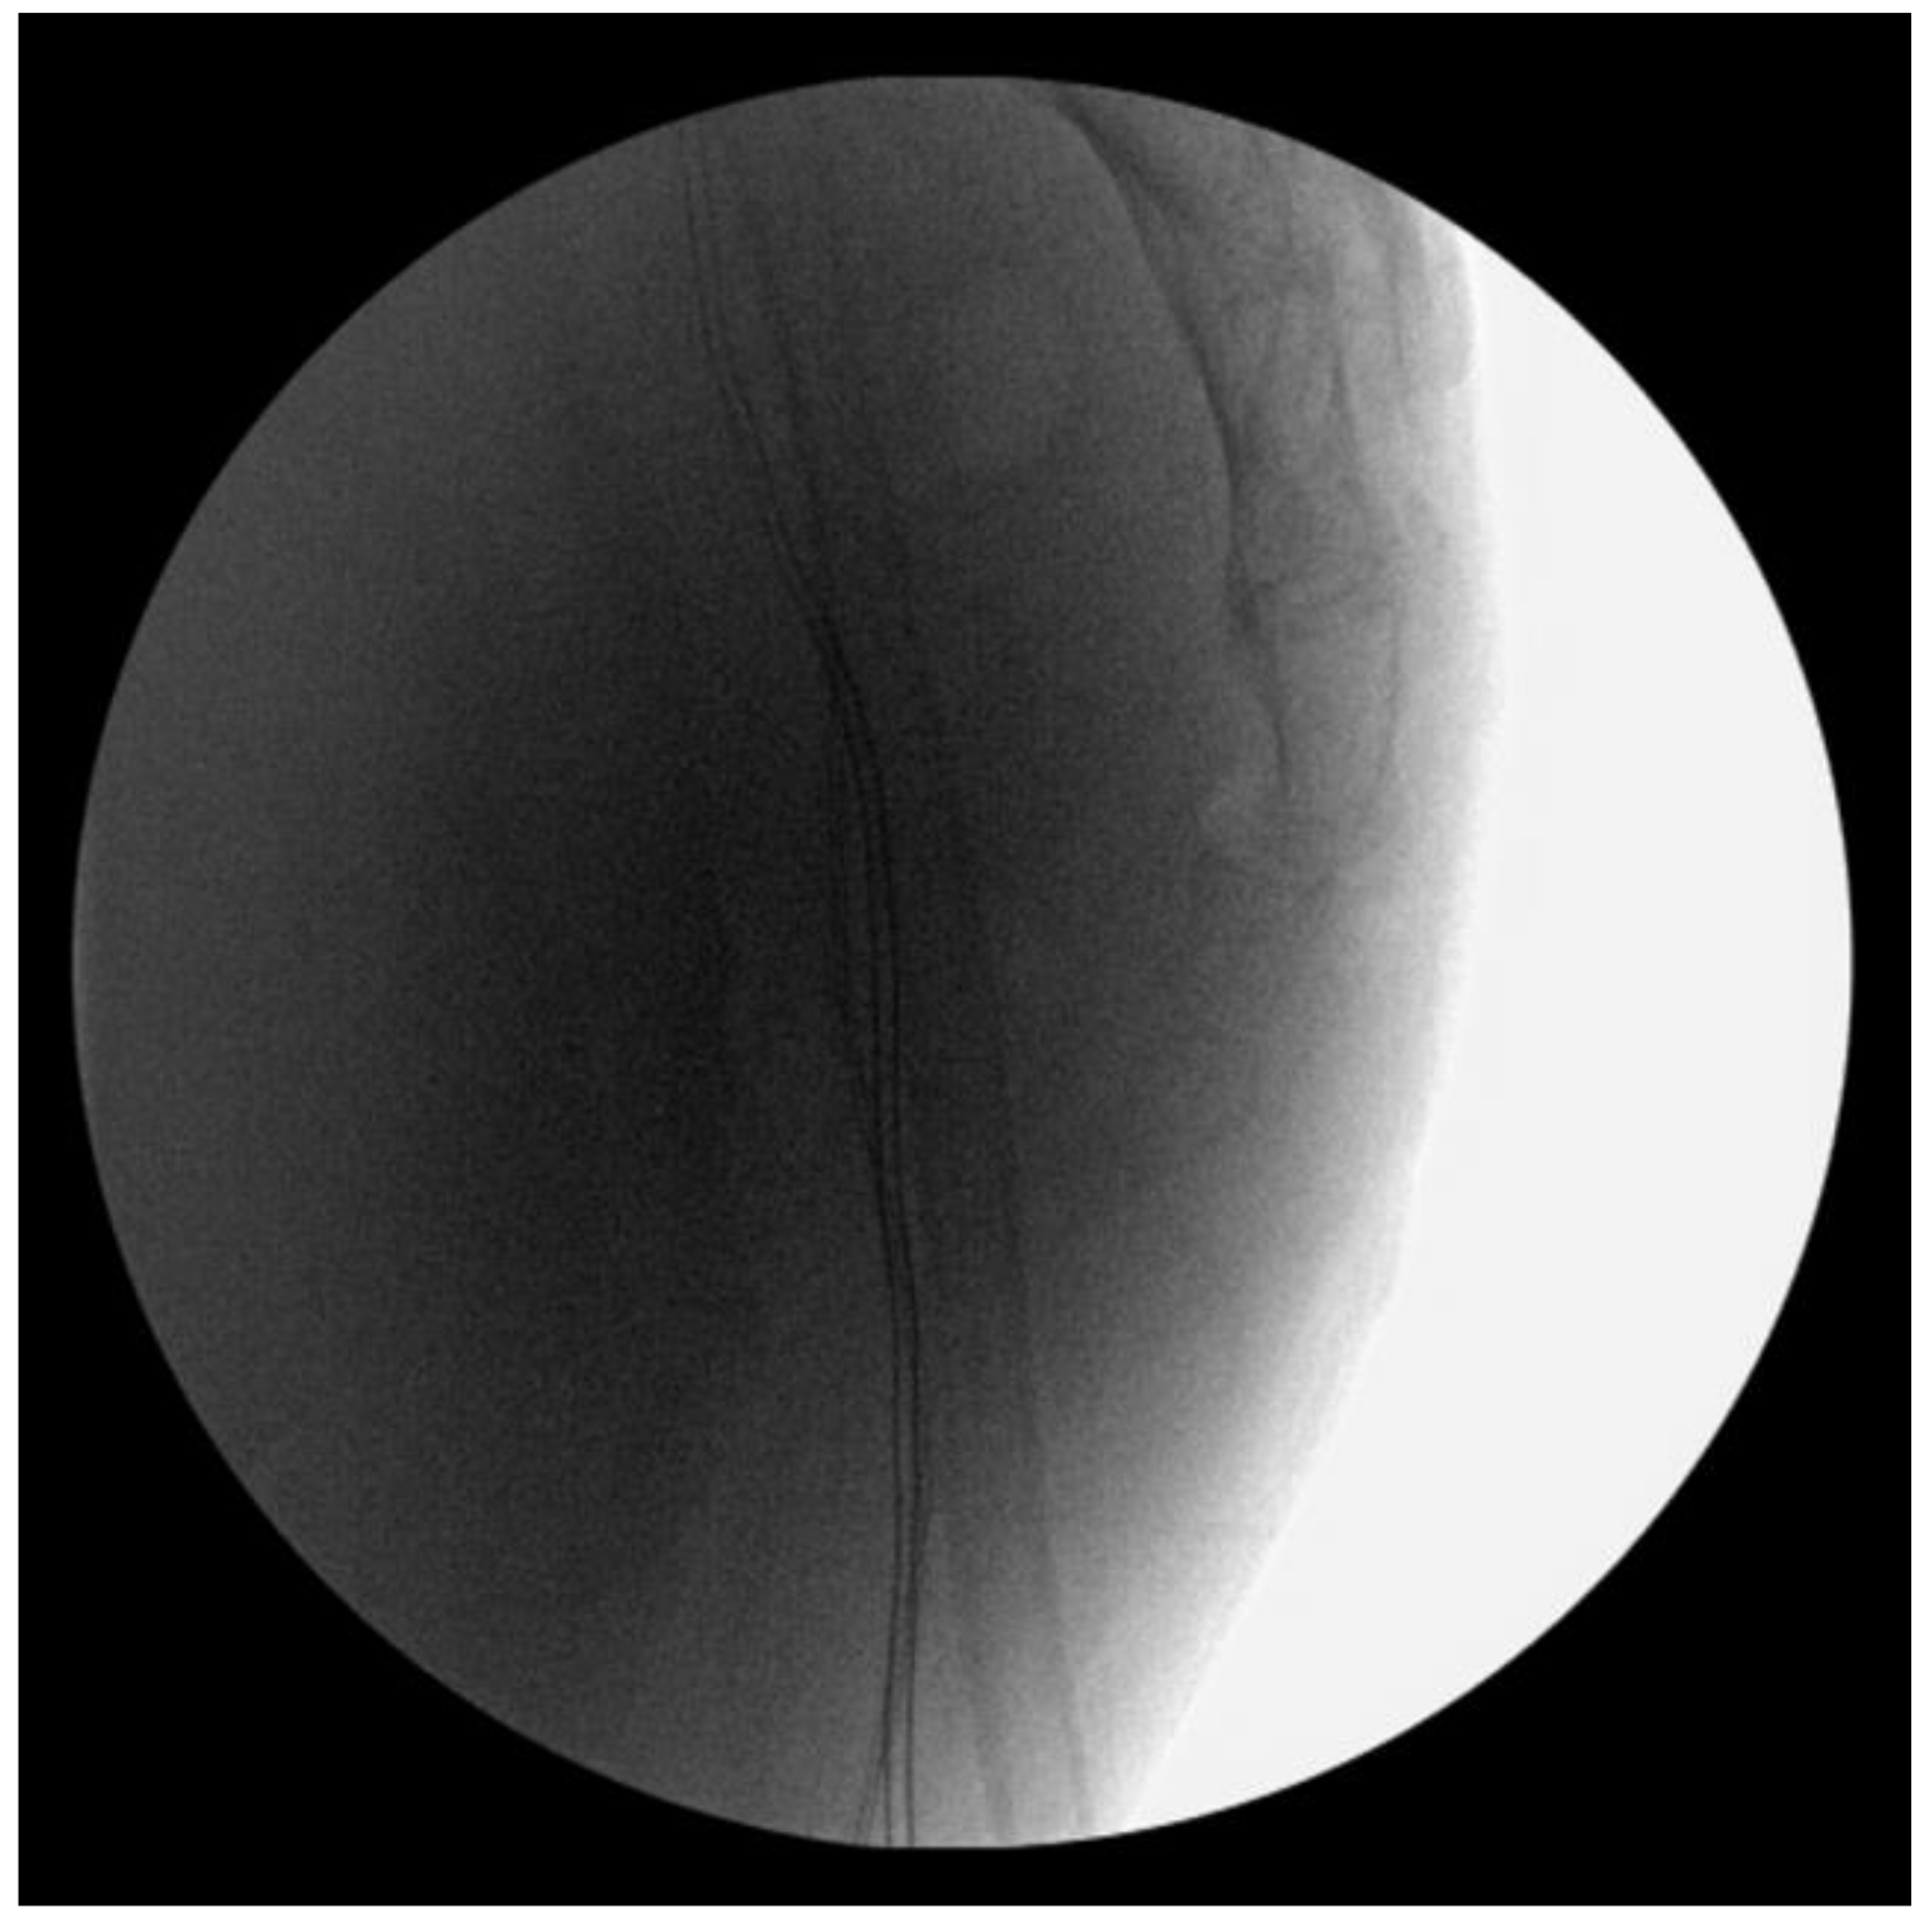

Intraoperative fluoroscopy confirmed a successful reduction. However, the coccyx tended to be subluxated anteriorly after removing the freer periosteal elevator (Figure 4).

Figure 4. Intraoperative fluoroscopy shows anterior subluxation of the coccyx after removing the freer periosteal elevator.